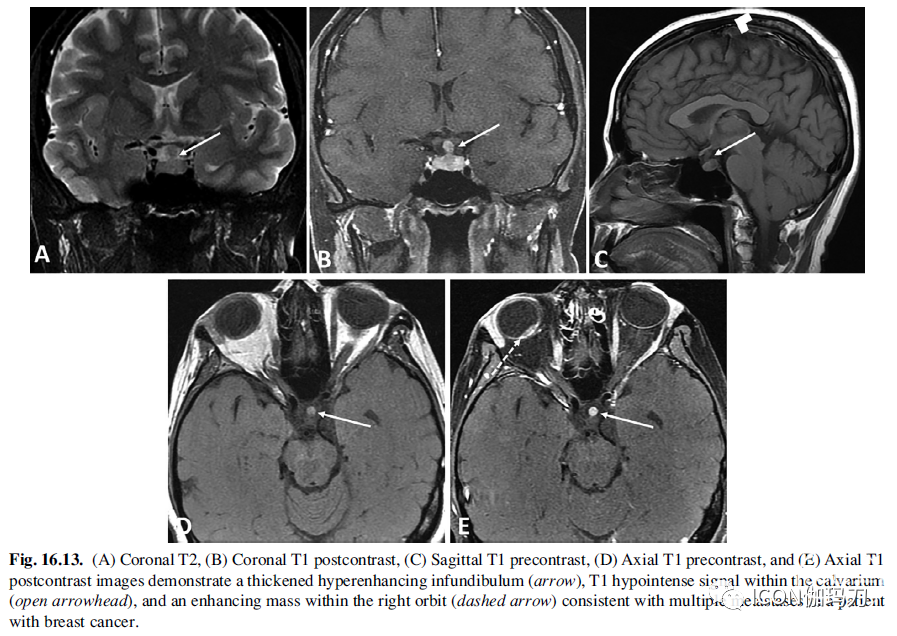

鞍区和鞍上转移瘤并不常见,转移瘤占鞍区肿块的1%。当超过50岁的患者出现新的或迅速扩大的鞍区肿块以及急性发作CDI时,它们是一个重要的考虑因素。乳腺癌和肺癌是最常见的相关原发肿瘤。对这些患者的初步评估应包括胸片和乳房检查。影像学表现多种多样,包括不均匀增强的肿块,在T1和T2上与大脑呈等信号,哑铃状肿瘤(鞍内和鞍上成分有薄的组织连接)或不规则结节状漏斗部增厚(图16.13)。存在骨质破坏和鞍区扩张,有助于区分大腺瘤和转移瘤。

图16.13.(A)冠状位T2, (B)冠状位T1增强,(C)矢状位T1平扫,(D)轴位T1平扫,和(E)轴位T1增强图像显示增厚的高度强化漏斗部(箭头),颅盖骨内T1低信号(开放箭头),右眼眶内强化肿块(虚线箭头),复合乳腺癌患者多发性转移瘤。